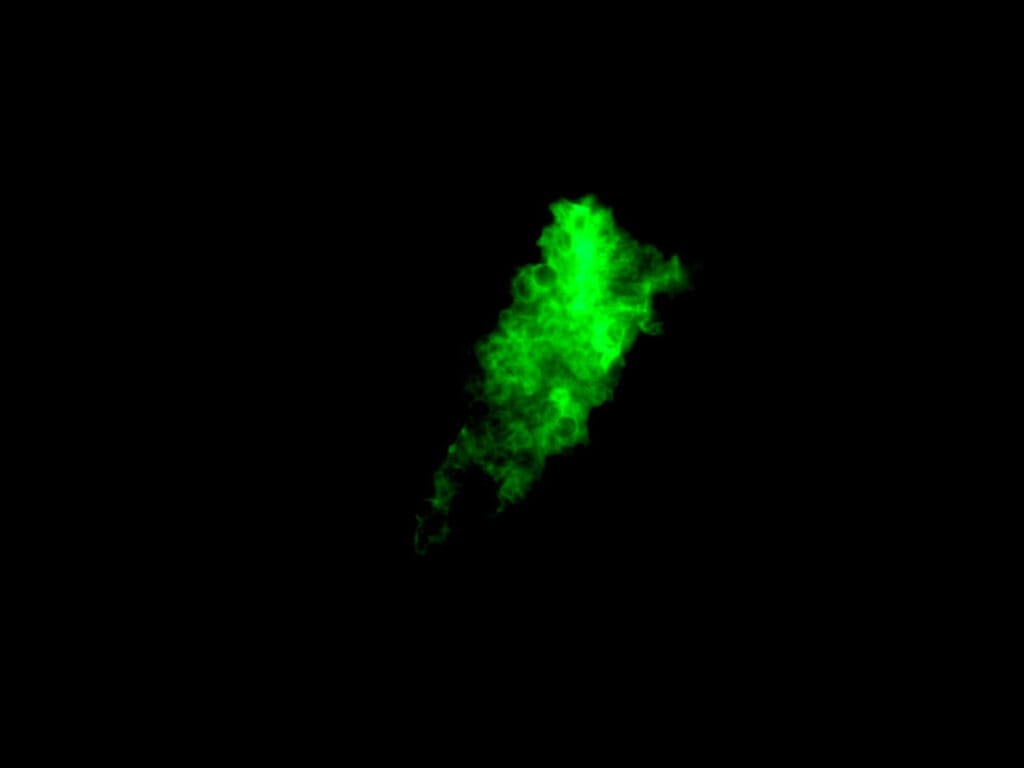

– 영상: 흉부 CT에서 양측성 간유리음영(ground-glass opacity)

Knipe H, Pneumocystis pneumonia. Case study, Radiopaedia.org (Accessed on 24 Jun 2025) https://doi.org/10.53347/rID-49397